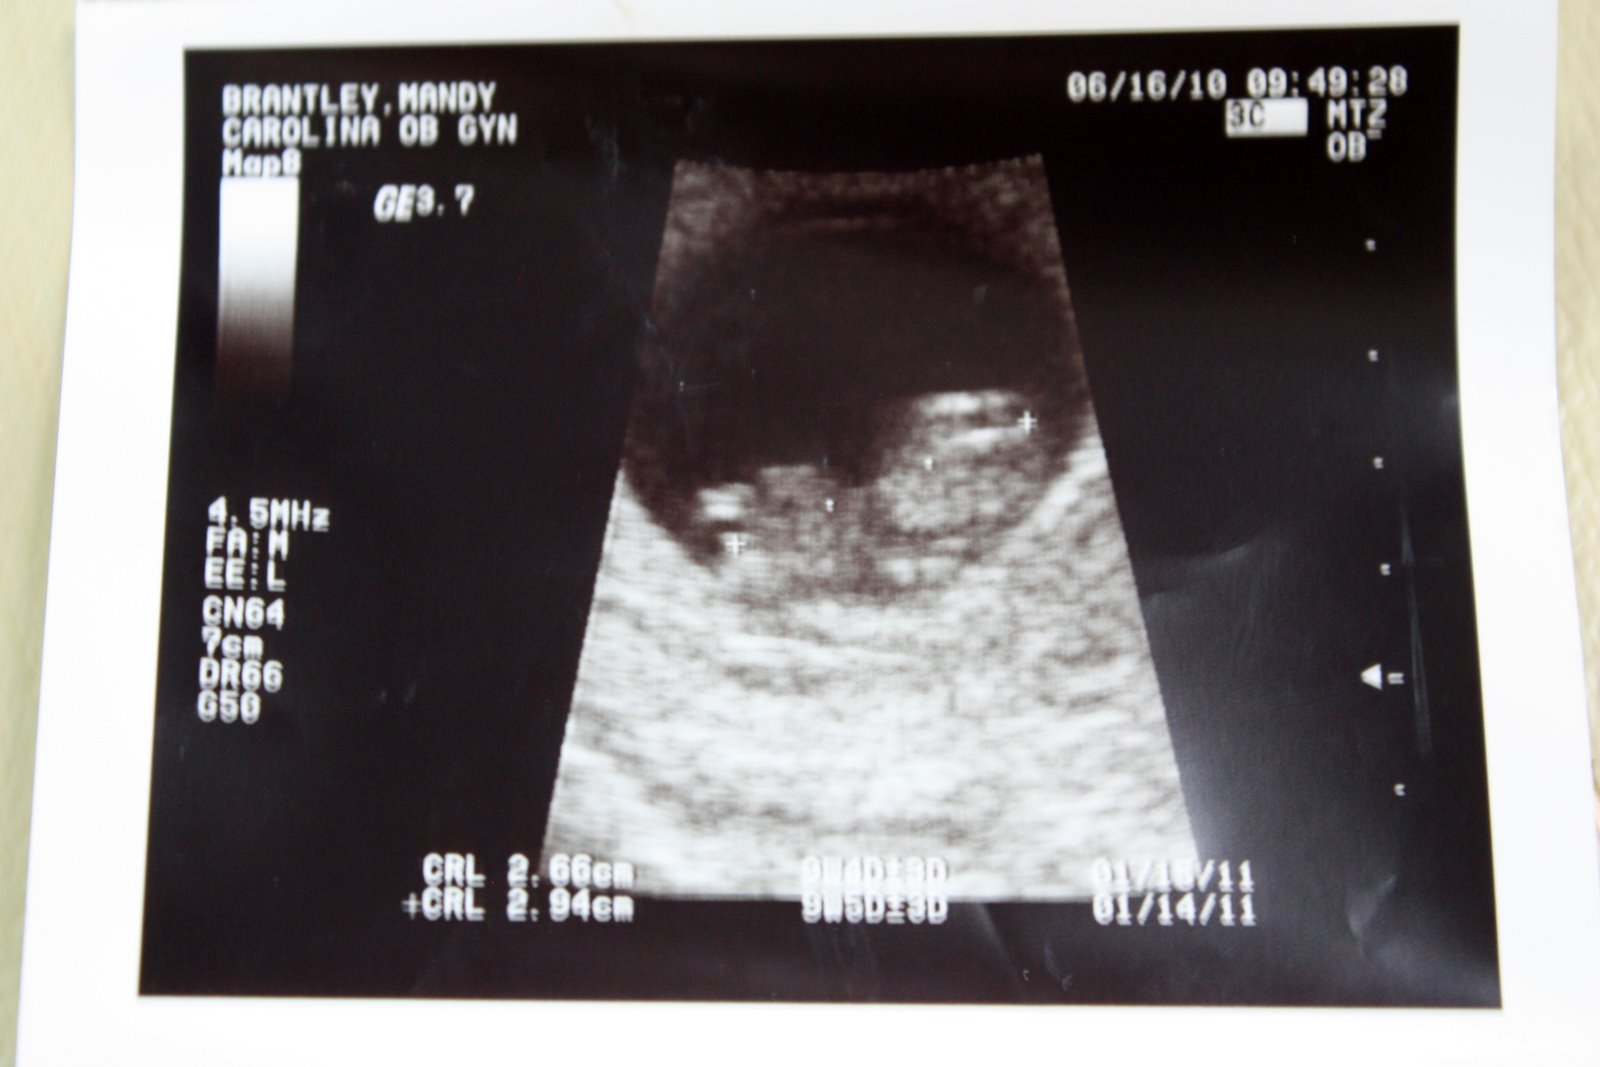

And I've hated keeping it a secret (I'm the worst secret-keeper ever). I told my family after this ultrasound, we can start telling people. If you look at the ultrasound, it has the dates of Jan 14 and Jan 15 as a due date. I'm going to stick with the 15th, but hope for the 9th!!!